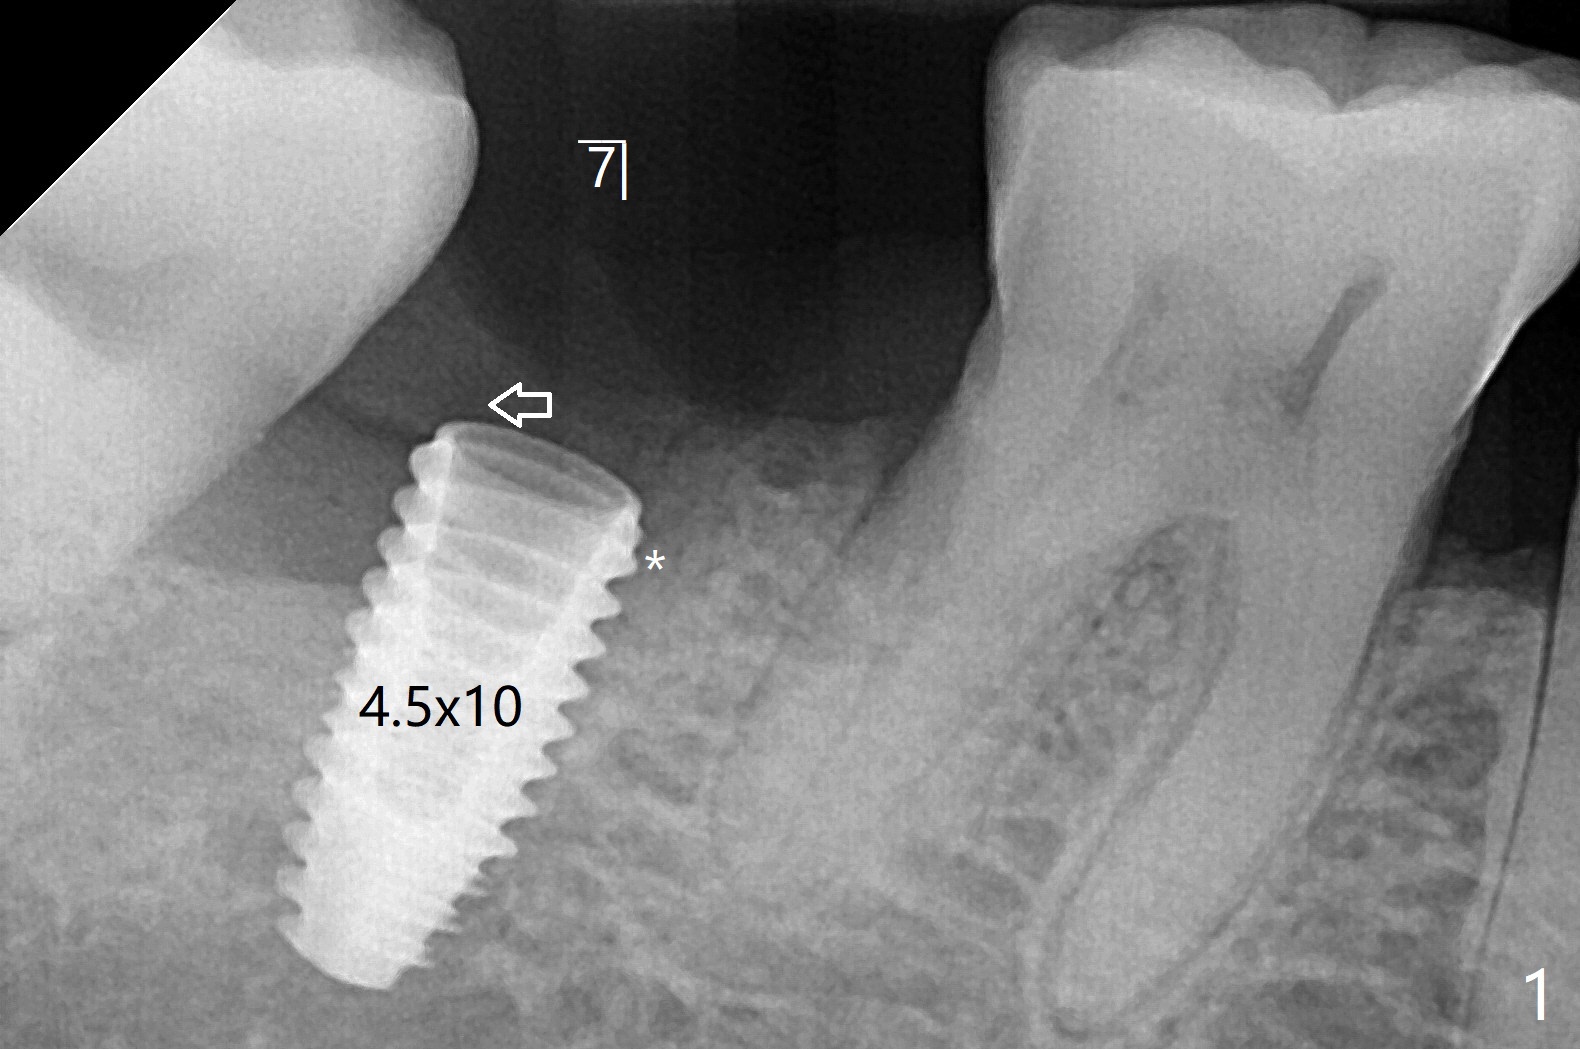

右下7有两个融合牙根,很长,起初(拔除后)有点害怕初步稳定性,使用导板完成近中窝4x10毫米钻洞后,植入4.5x10毫米报废植体,当时没有发觉植体已经发生远中偏移(图一:箭头,因为近中牙槽嵴高(*),而中隔缺失)。当正式植体植入后(图二),病人发现偏移,术者觉得临床上还可以,以为可能因为X光拍摄角度问题。再次放入粘性骨粉后,咬翼片拍摄注意角度问题,但是偏移仍存在(图三)。为了防止偏移现象,要么设计时有意往阻力大的地方偏移少许(例如这个病例1毫米,图四),要么发现偏移后,有意使用侧方切割钻头(Lindamann bur)去除阻力(近中骨)。如果扭力低,包埋植体。术后一个月取出临时牙冠,骨粉仿佛成为牙龈一部分(图五:*),之后暂时粘固粉固定牙冠。术后五个月骨粉好像与邻牙牙根和植体愈合(图六:*)。永久性粘固后,基台螺丝拧紧20Ncm。